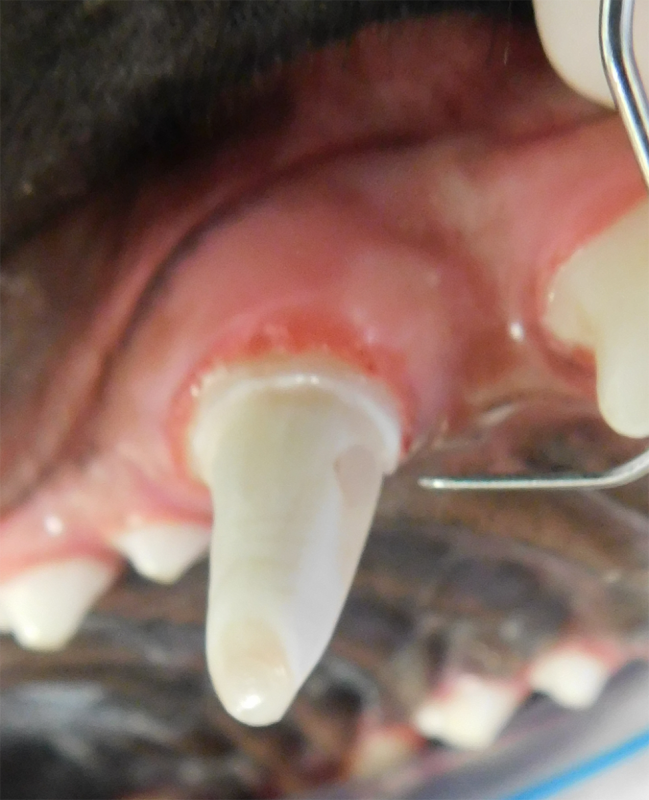

Vital Pulp Therapy

Young dogs less than 1 year of age that have very recently (less than 48 hours) fractured a tooth may be a candidate for vital pulp therapy. This procedure keeps the tooth alive and is very minimally invasive. For best results, this procedure should be performed within 48 hours of the tooth fracture. If your pet is not a candidate for this procedure, root canal therapy can still be performed to preserve the structure and function of the tooth. Vital pulp therapy can also be used to treat malocclusions.